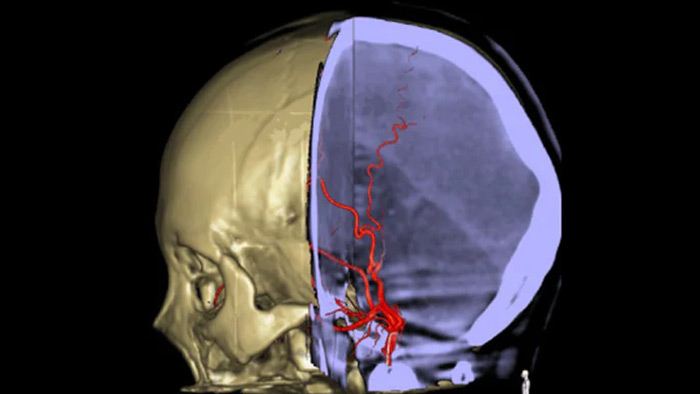

SmartCT Vaso позволяет проводить визуализацию за пределами тромба с помощью перипроцедурного создания изображений дистальных сосудов при ишемическом инсульте. SmartCT Vaso — это метод сбора данных, основанный на получении КТ-изображений с помощью конического пучка и внутриартериальной инъекции контраста. Технология позволяет проводить визуализацию за пределами тромба с помощью перипроцедурного создания изображений дистальных сосудов при ишемическом инсульте. При ретроградном наполнении становится видна структура сосудов до и после тромба. 3D-схема сосудов SmartCT Vaso может использоваться при визуализации устройств для извлечения тромба.